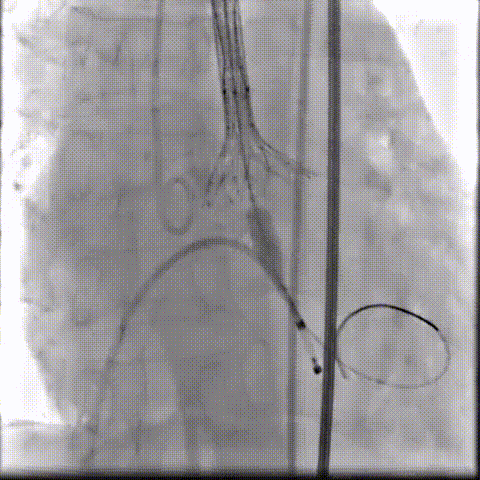

术中影像

根部造影可见返流;20mm球囊预扩,LCA灌注缝隙狭小

预置LCA保护;第一次释放,

团状钙化挤压导致瓣膜(AV23)少量下滑

回收后重新定位,第二次释放,

瓣膜(AV23)深度仍未达到最佳预期

完全回收,第三次定位释放,瓣膜(AV23)位置良好

瓣膜工作位释放“烟囱支架”;

瓣膜(AV23)完全释放后,“烟囱支架”后扩

最终造影,“烟囱支架”显影清晰,瓣膜形态及LCA灌注良好